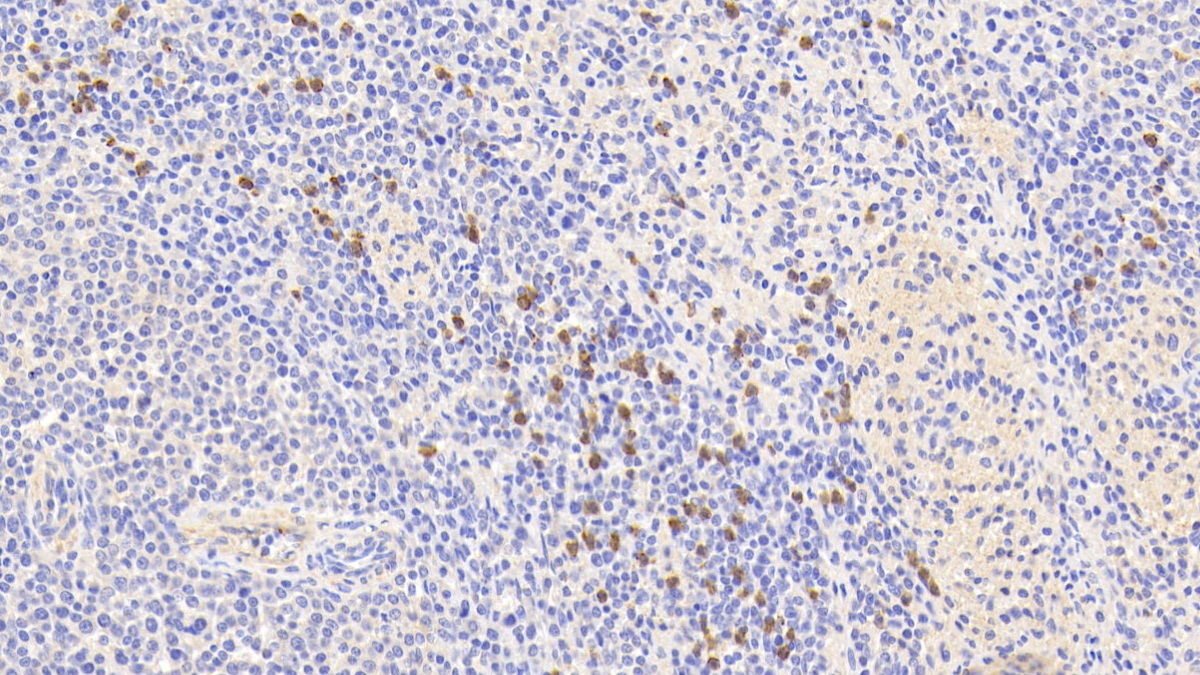

Polyclonal Antibody to S100 Calcium Binding Protein A9 (S100A9)

Product No.: PAB793Hu01

Organism species: Homo sapiens (Human)

Monoclonal Antibody to S100 Calcium Binding Protein A9 (S100A9)

Product No.: MAB793Hu22

Organism species: Homo sapiens (Human)